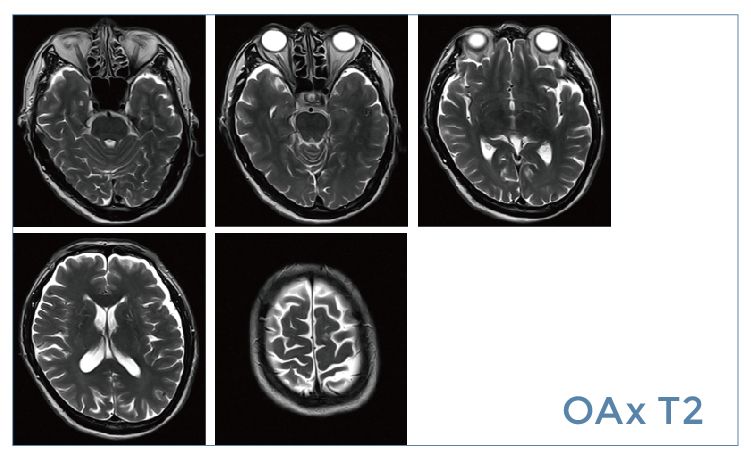

【朗润影像档案】20190524磁共振影像病例结果讨论

【朗润影像档案】磁共振影像病例分享(编号20190524)